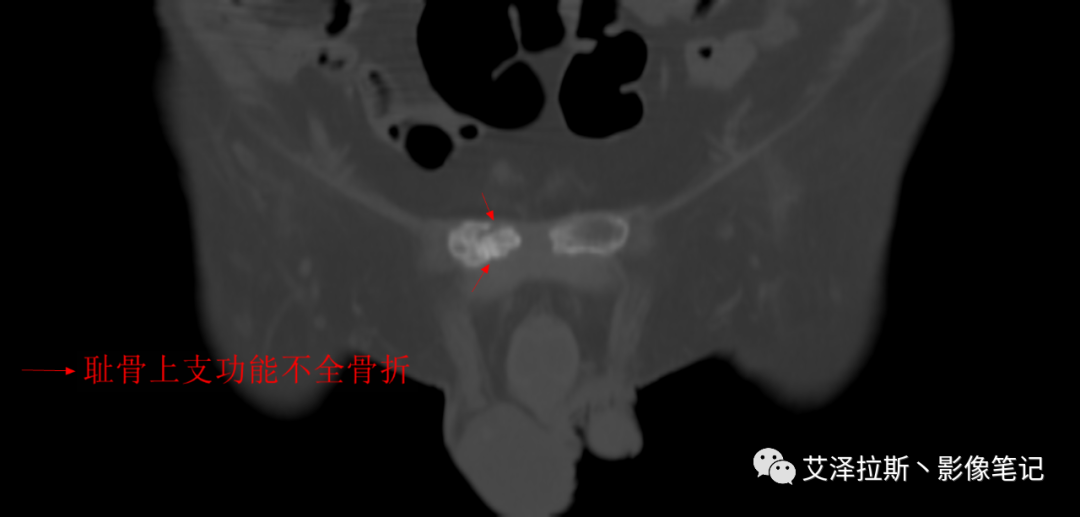

病例2:患者,女性,69岁,老年性骨质疏松症。

CT平扫:

②骨折线位于骶孔外侧(如下图,主要发生于1区),通常可能会伴随耻骨的功能不全骨折(如:病例2 右侧耻骨上支骨折,L5双侧横突骨折);